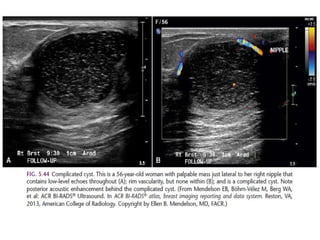

Breast imaging power point